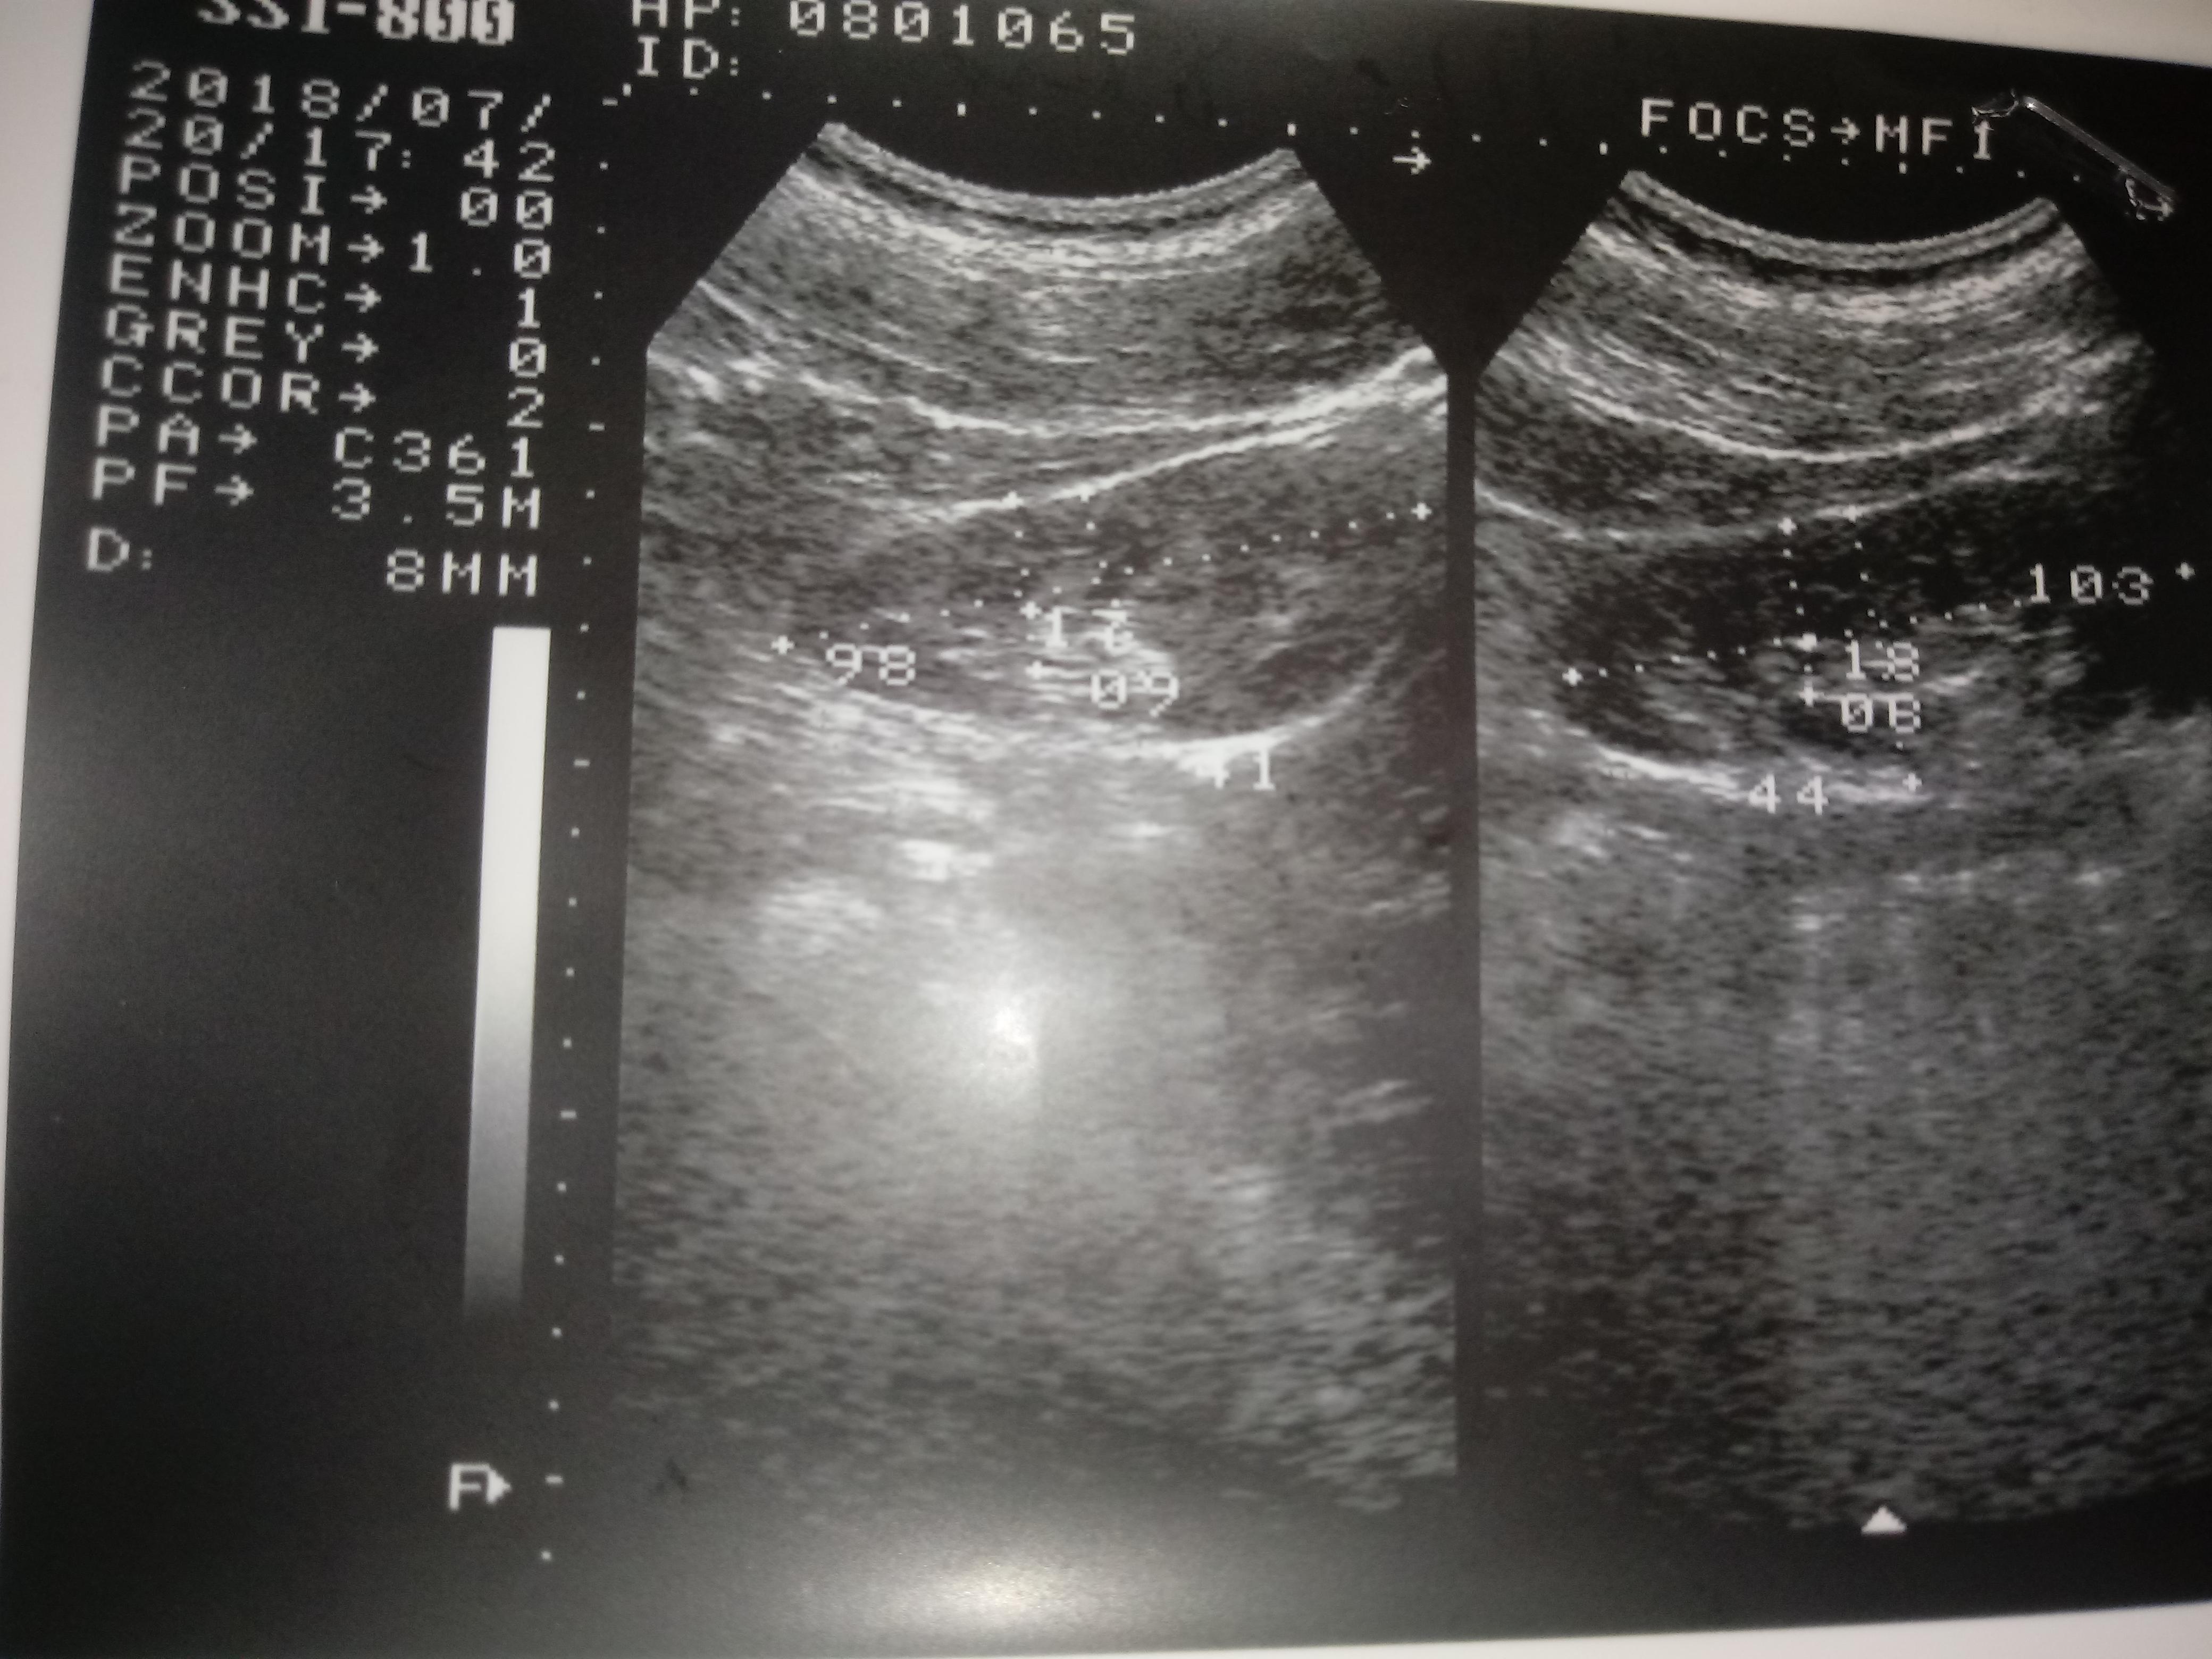

Добрый день! Моему сыну 15 лет. В его моче обнаружено большое количество эритроцитов. Узи почек показало "МКД обеих почек и киста правой почки". Назначение терапевта: уродан 1 ч/л×100 мл.×2 р.д. 30 дней,конефрон 1 таб×3 р.д. 30 дней. Скажите, пожалуйста, насколько это серъезно? Дело в том, что мой сын поступает в военную школу. Сами понимаете, там физические нагрузки. Можно ли нам там учиться с таким диагнозом? И какое лечение посоветуете? Нужно ли нам дополнительно сделать КТ или МРТ?

Ответ врача